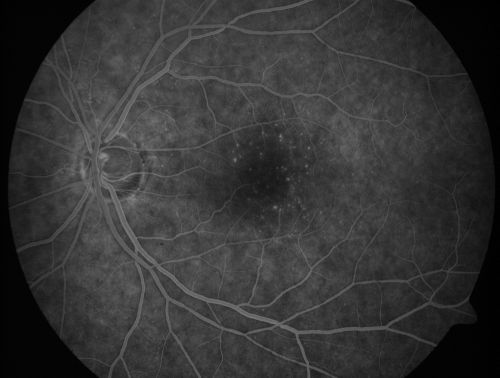

Juxtafoveal Telangiectasis - After Hemorrhage Absorbed Right Eye with Avastin Injections

73-year-old woman has juxtafoveal retinal telangiectasis in both eyes.  The right eye has stage 5 disease.  Her last Avastin treatment in the right eye was in 6 months ago.  The right eye has been the worst of her two eyes for years.

VISUAL ACUITY: Vision OD is 20/200, OS is 20/50.